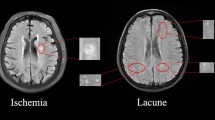

White matter hyperintensity (WMHI) lesions on MR images are an important indication of various types of brain diseases that involve inflammation and blood vessel abnormalities. Automated quantification of the WMHI can be valuable for the clinical management of patients, but existing automated software is often developed for a single type of disease and may not be applicable for clinical scans with thick slices and different scanning protocols. The purpose of the study is to develop and validate an algorithm for automatic quantification of white matter hyperintensity suitable for heterogeneous MRI data with different disease types.

We developed and evaluated “DeepWML”, a deep learning method for fully automated white matter lesion (WML) segmentation of multicentre FLAIR images. We used MRI from 507 patients, including three distinct white matter diseases, obtained in 9 centres, with a wide range of scanners and acquisition protocols. The automated delineation tool was evaluated through quantitative parameters of Dice similarity, sensitivity and precision compared to manual delineation (gold standard).

The overall median Dice similarity coefficient was 0.78 (range 0.64 ~ 0.86) across the three disease types and multiple centres. The median sensitivity and precision were 0.84 (range 0.67 ~ 0.94) and 0.81 (range 0.64 ~ 0.92), respectively. The tool’s performance increased with larger lesion volumes.

DeepWML was successfully applied to a wide spectrum of MRI data in the three white matter disease types, which has the potential to improve the practical workflow of white matter lesion delineation.